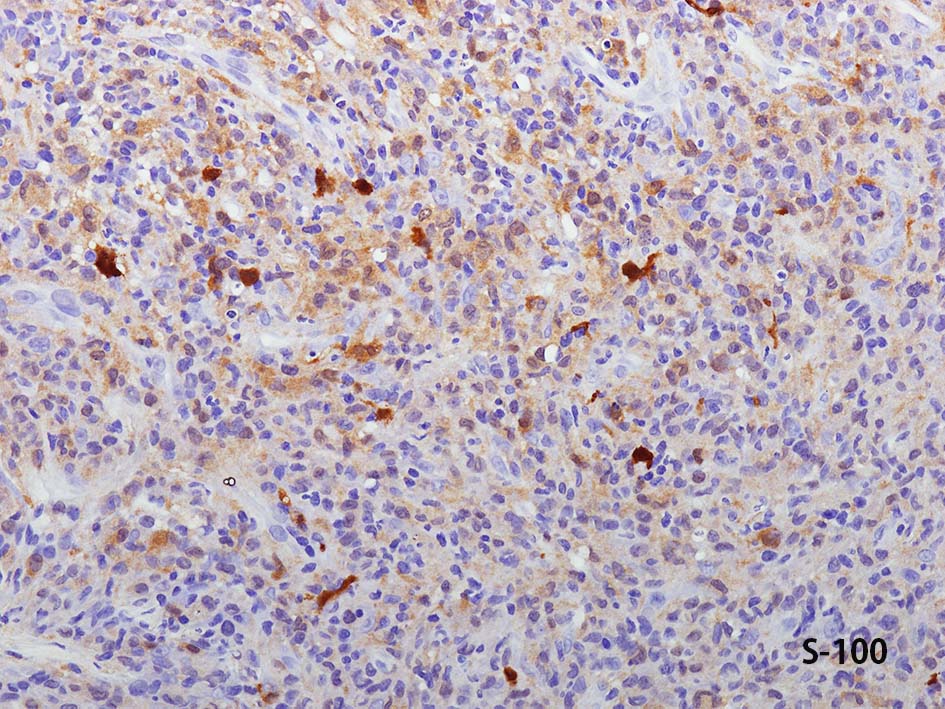

CD20, PAX5, CD3, CD5 リンパ球マーカは陰性. Dendritic cell marker (CD1a, CD123, Langerin, etc)は陰性. S-100, CD168, CD68(KP-1)が陽性. 組織球増殖病変と考えられた. foamy macrophageやgiant cellsはほとんど認められない. 高異型度, 多型細胞の出現はないが, MIB-1 LIが高く, mitosisも増加している, 悪性の心配あり, 治療方針の決定のため consultationを行った.

IHCの拡大像. Factor XⅢaの免疫染色画像もここに掲載する.